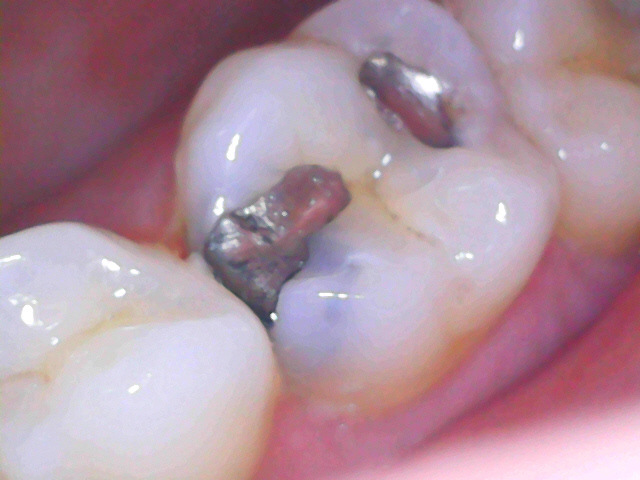

Initial